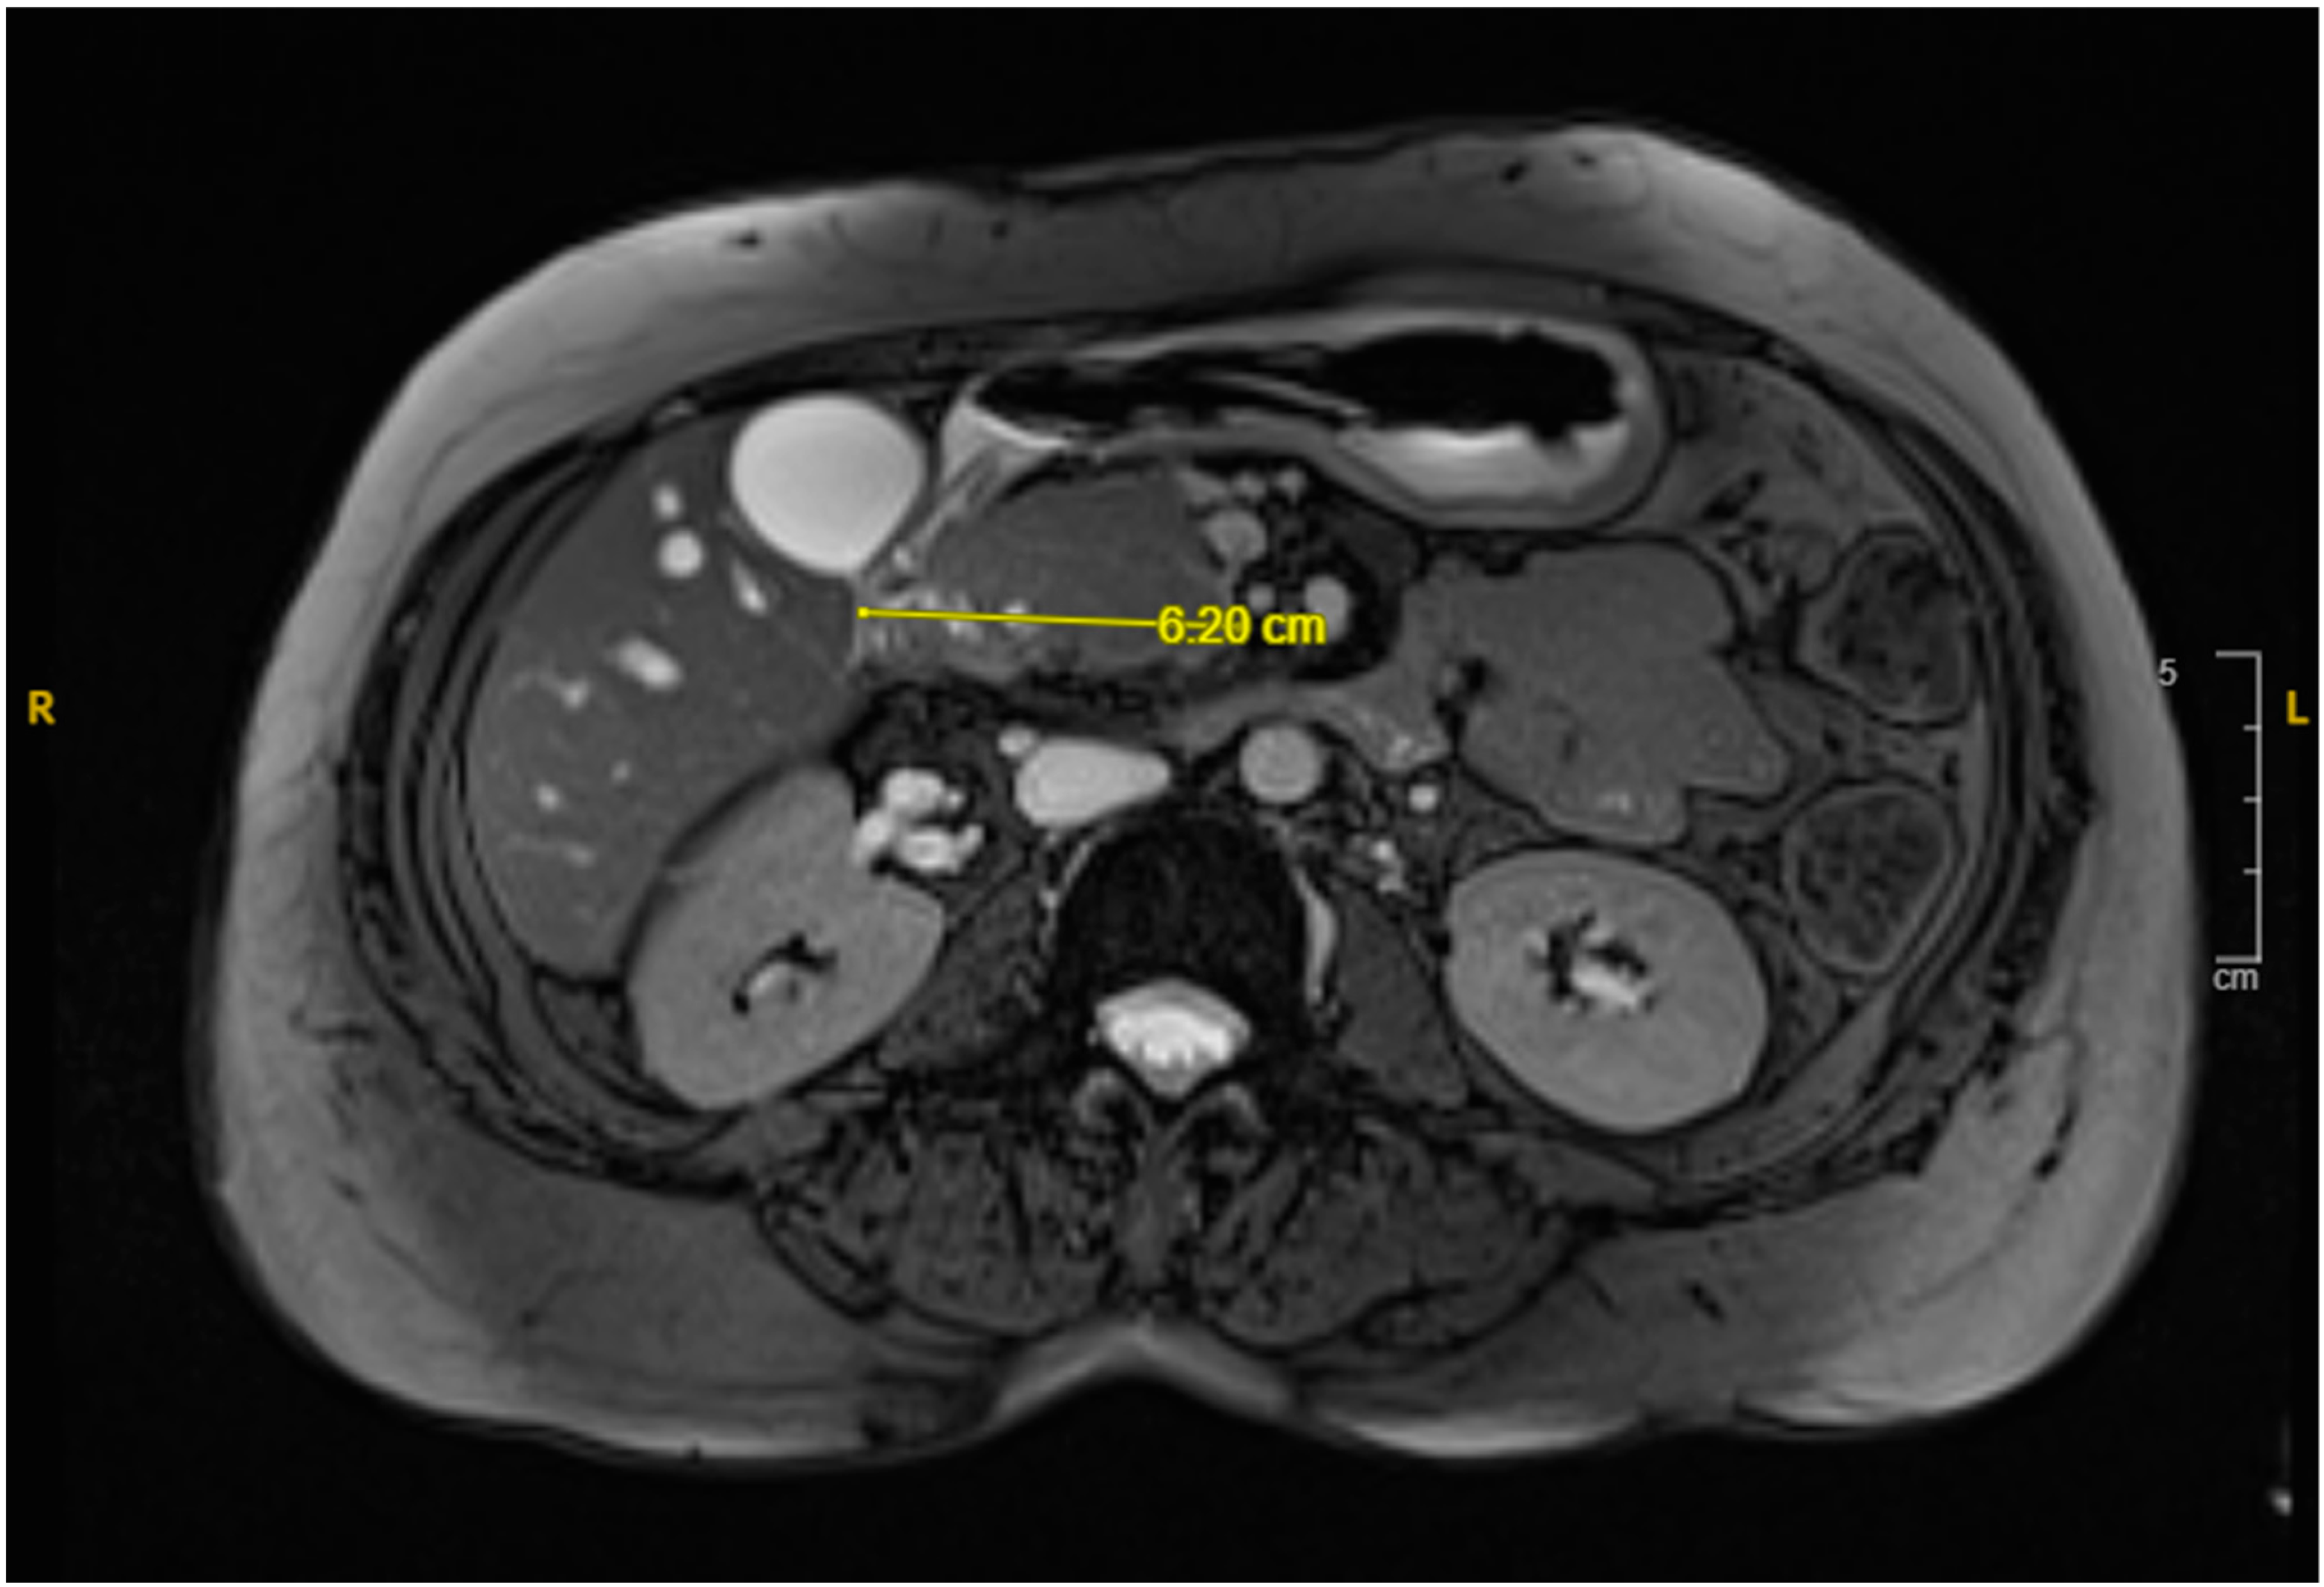

Over the following days, the NG tube suction output remained significant (1–1.5 L daily), and the liver function tests (LFTs) showed a slow uptrend with mixed hepatocellular and cholestatic pattern, likely due to extrinsic compression on the distal common bile duct from the duodenal hematoma. NJ feeding continued, with close monitoring of NG suction output. The patient tolerated the NJ feeds well, and the LFT showed slight improvement. A repeated MRI revealed a reduction in the hematoma size (from 7.8 cm × 5.8 cm to 6.2 cm × 2.5 cm as shown in Figure 3), along with decreased duodenal wall thickness and hyperenhancement. A follow-up EGD revealed improved non-bleeding gastric ulcer and successful passage of the scope through the second portion of the stenosed duodenum.

Figure 3. MRI cholangiogram revealing interval decrease in size of the duodenal hematoma to 6.2 cm in its widest diameter.